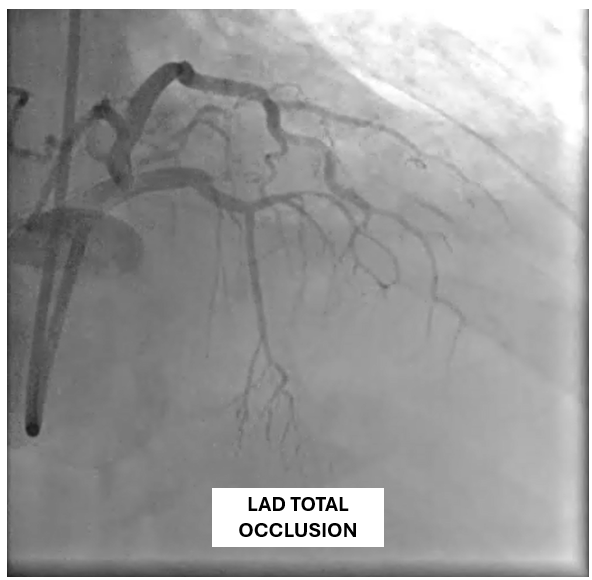

The patient underwent coronary angiography, where the team attempted to reopen the previously stented proximal mid LAD that had become occluded. After multiple revascularization efforts from ballooning to placing a ne DES in the mid LAD. A type III perforation occurred in the distal LAD during balloon inflation. Despite immediate measures including balloon tamponade and covered stent deployment, the perforation remained visible on follow-up angiography.

A covered stent was deployed in the distal LAD in an attempt to seal the coronary perforation; however, angiography showed that the Type III perforation persisted despite the intervention. Additional balloon inflation within the stent was performed, but the leakage could not be completely sealed. The patient remained hemodynamically stable without signs of cardiac tamponade or pericardial effusion. The following day, repeat coronary angiography was conducted to reassess the condition, which confirmed persistent contrast extravasation from the LAD into the left ventricular cavity, indicating the formation of a coronary–ventricular fistula. Given the hemodynamic significance and the risk of progressive left ventricular dysfunction due to continuous shunting, a multidisciplinary decision was made to proceed with surgical correction. The patient subsequently underwent successful LAD–LV fistula patch repair combined with. Surgical repair remains the definitive management for such cases, and early recognition with timely intervention is crucial to restore cardiac function and prevent irreversible myocardial damage.